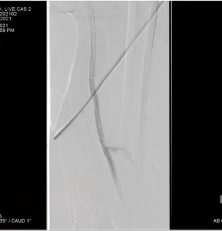

Mustapha CTO Crossing Retrograde Pedal Access

Video AMP 2021

07/22/2021

In this Live CLI case, endovascular intervention is performed via the brachial and pedal arteries in a patient with a complex CFA and SFA CTO with limited access options. Multiple crossing and treatment modalities are utilized in this case to...